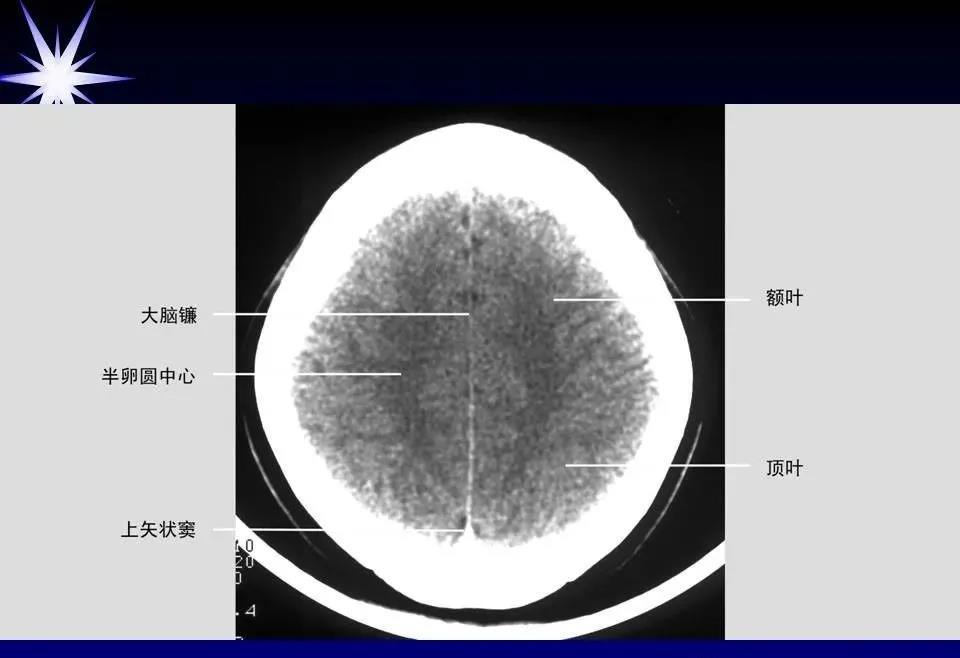

来源:华夏影像诊断中心